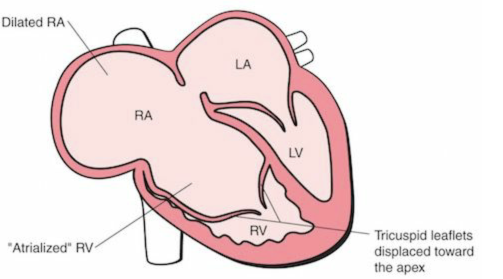

Anomalie d’Ebstein

- Déplacement inférieur de la valve tricuspide

- Dilatation massive de l’OD (signe du carton)

- VD “atrialisé”